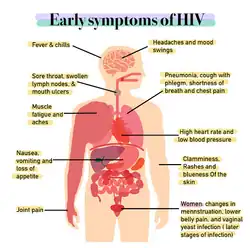

The stages of HIV infection are acute infection (also known as primary infection), latency, and AIDS. Acute infection lasts for several weeks and may include symptoms such as fever, swollen lymph nodes, inflammation of the throat, rash, muscle pain, malaise, and mouth and esophageal sores. The latency stage involves few or no symptoms and can last anywhere from two weeks to twenty years or more, depending on the individual. AIDS, the final stage of HIV infection, is defined by low CD4+ T cell counts (fewer than 200 per μL), various opportunistic infections, cancers, and other conditions.

During this period (usually days to weeks post-exposure) fifty to ninety percent of infected individuals develop an influenza or mononucleosis-like illness called acute HIV infection (or HIV prodrome),[2][3] the most common symptoms of which may include fever, lymphadenopathy, pharyngitis, rash, myalgia, malaise, mouth and esophageal sores, and may also include, but less commonly, headache, nausea and vomiting, fatigue, ulcers in the mouth or on the genitals, enlarged liver/spleen, weight loss, thrush, night sweats and diarrhea and neurological symptoms. Infected individuals may experience all, some, or none of these symptoms.[4] The duration of symptoms varies, averaging 28 days and usually lasting at least a week.[5]